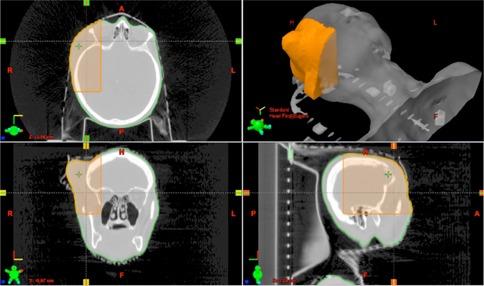

The purpose of this paper is to demonstrate that an inexpensive 3D printer can be used to manufacture patient-specific bolus for external beam therapy, and to show we can accurately model this printed bolus in our treatment planning system for accurate treatment delivery. Percent depth-dose measurements and tissue maximum ratios were used to determine the characteristics of the printing materials, acrylonitrile butadiene styrene and polylactic acid, as bolus material with physical density of 1.04 and 1.2 g/cm3, and electron density of 3.38 × 10²³ electrons/cm3 and 3.80 × 10²³ electrons/ cm3, respectively. Dose plane comparisons using Gafchromic EBT2 film and the RANDO phantom were used to verify accurate treatment planning. We accurately modeled a printing material in Eclipse treatment planning system, assigning it a Hounsfield unit of 260. We were also able to verify accurate treatment planning using gamma analysis for dose plane comparisons. With gamma criteria of 5% dose difference and 2 mm DTA, we were able to have 86.5% points passing, and with gamma criteria of 5% dose difference and 3 mm DTA, we were able to have 95% points passing. We were able to create a patient-specific bolus using an inexpensive 3D printer and model it in our treatment planning system for accurate treatment delivery.

本文的目的是证明一台低成本的3D打印机可用于制造适用于外照射治疗的个体化组织等效填充物,并表明我们能够在治疗计划系统中精确模拟这种打印的填充物,以实现精确的治疗实施。使用百分深度剂量测量和组织最大剂量比来确定打印材料丙烯腈-丁二烯-苯乙烯(ABS)和聚乳酸(PLA)作为填充物材料的特性,其物理密度分别为1.04 g/cm³和1.2 g/cm³,电子密度分别为3.38×10²³电子/cm³和3.80×10²³电子/cm³。使用Gafchromic EBT2胶片和RANDO体模进行剂量平面比较,以验证精确的治疗计划。我们在Eclipse治疗计划系统中精确模拟了一种打印材料,为其赋予260的Hounsfield单位。我们还能够使用伽马分析进行剂量平面比较来验证精确的治疗计划。在伽马标准为5%剂量差异和2 mm剂量-距离容差(DTA)的情况下,我们能够使86.5%的点通过;在伽马标准为5%剂量差异和3 mm DTA的情况下,我们能够使95%的点通过。我们能够使用一台低成本的3D打印机创建个体化组织等效填充物,并在我们的治疗计划系统中对其进行模拟,以实现精确的治疗实施。